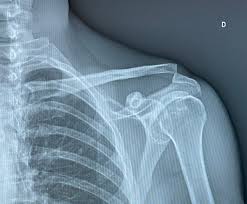

Sígno de la tecla

Hallazgo clínico característico de ciertas luxaciones acromiovasculares (grado 3)

Cuando presionas hacia abajo la clavícula distal (en la articulación acromioclavicular) esta desciende, pero al soltarla vuelve a subir inmediatamente, como si fuera una tecla de piano.

¿Por qué ocurre?

Porque los ligamentos coracoclaviculares y/o acromioclaviculares están rotos, permitiendo que la clavícula quede elevada y móvil.

Qué indica

Sugiere inestabilidad importante en la articulación acromioclavicular.

Se asocia principalmente a luxación AC grado III o superior.